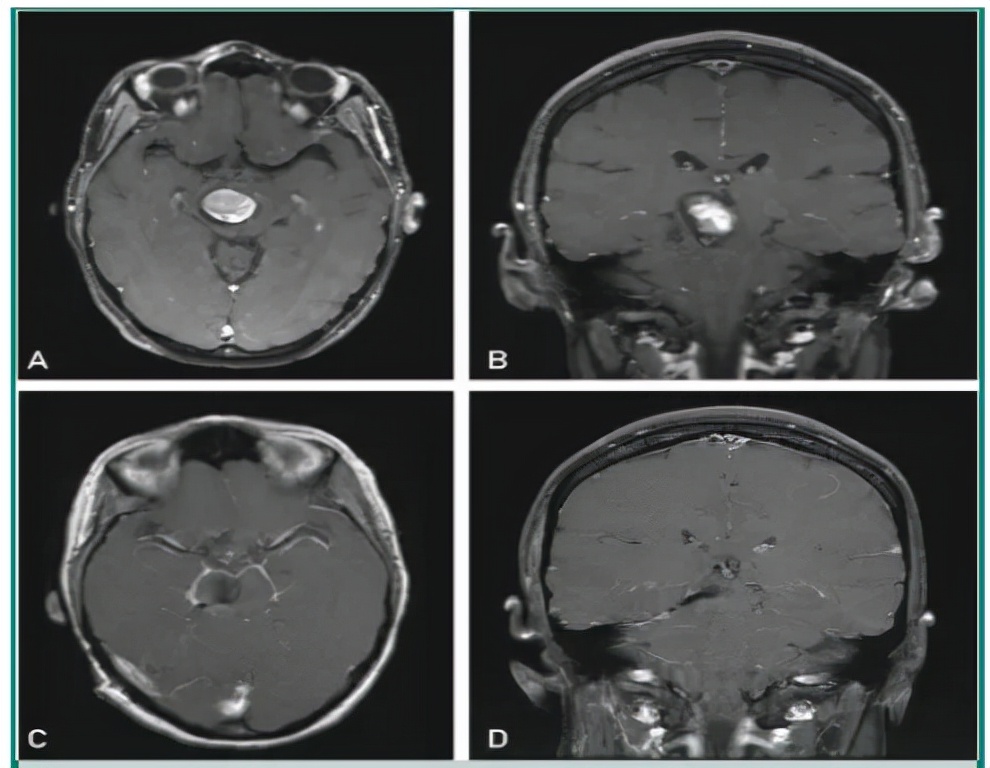

图2:颅内不同部位的海绵状血管瘤病灶

大约80%的患者是散发病例。通常情况下,患者会有一个单一的病变,往往同时伴有发育性静脉异常(DVA)。一些数据支持DVA在影响出血风险方面的潜在作用。大约30%的散发性海绵状血管瘤患者在标准MRI序列中会有相关的发育性静脉异常。

多达20%的病人是家族性病例。导致家族性海绵状血管瘤的3种已知的蛋白编码基因是:KRIT1(CCM1)、Malcavernin(CCM2)和PDCD10(CCM3)(见图3)。这些基因调节参与内皮细胞紧密连接的稳定性、细胞增殖和血管生成的信号通路。家族性海绵状血管瘤通常以不伴相关发育性静脉异常的多发性海绵状血管瘤为特征,但也存在与发育性静脉异常相关的家族性海绵状血管瘤的罕见病例。